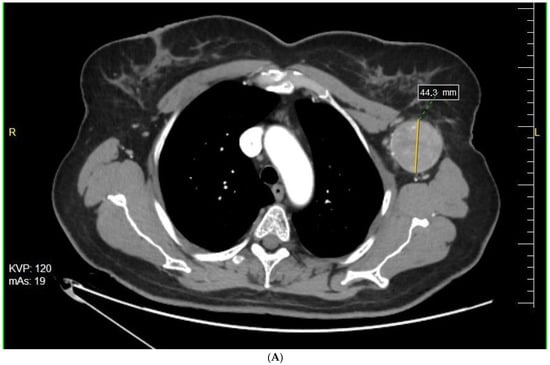

Forty-six subsequent patients started neoadjuvant therapy with BRAF +/− MEK inhibitors between 1 October 2014 and 30 June 2020. At the time of neoadjuvant treatment initiation, 14 patients had disease recurrence, while 14 had extensive metastases in the regional lymph nodes (Table 2, Figure 1).

Figure 1.

Response to preoperative BRAFi/MEKi therapy—the extent of the metastatic tumor in the left axilla before (A) and after (B) targeted therapy (Figure by Pawel Rogala).

37 patients were treated with dabrafenib and trametinib, 3 patients were treated with vemurafenib and cobimetinib, 5 with vemurafenib monotherapy, and 1 with dabrafenib monotherapy. The median time of BRAFi/MEKi treatment before surgery was 16 weeks. All patients underwent surgery with 78% microscopically margin-negative resection (R0) resections. The therapeutic lymph node dissection (TLND) was performed in 18 patients. Other surgery procedures included metastasectomy and recurrence resection (Table 3).